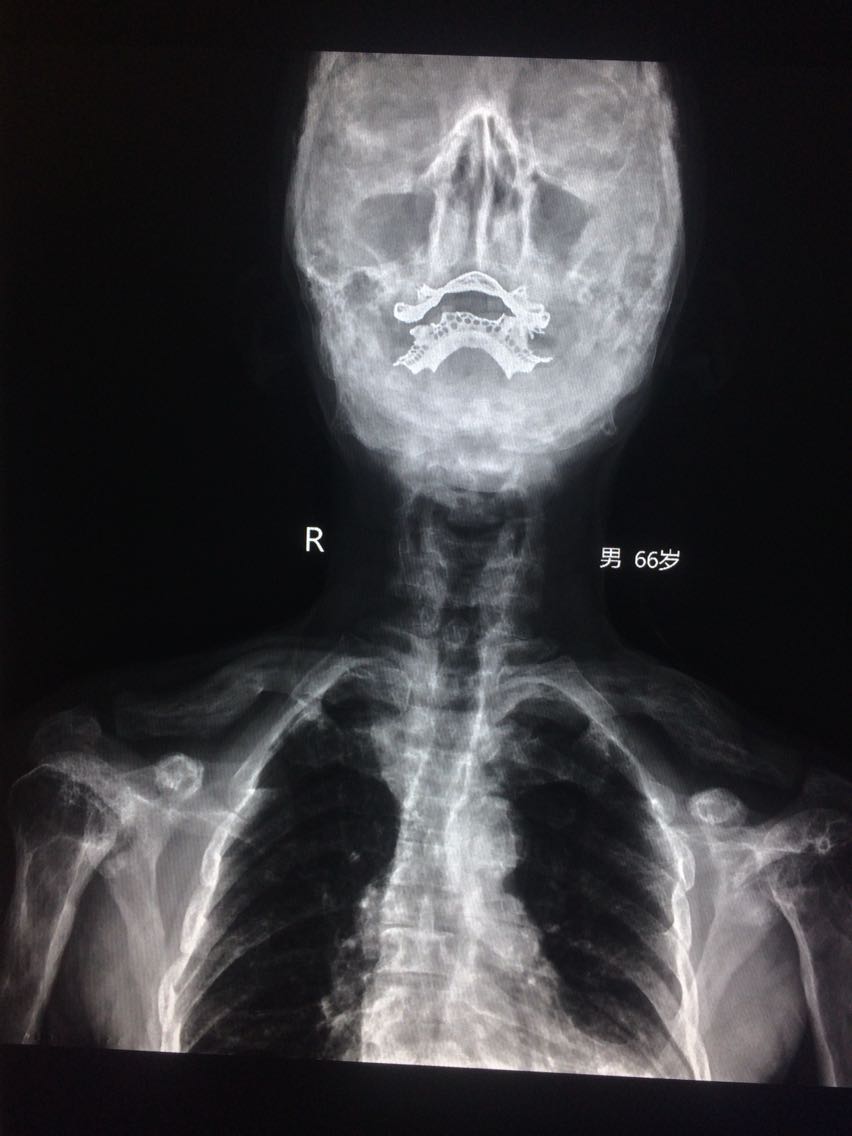

男,65岁 颈部外伤2天。 2天前,在家干农活时,不小心颈部受伤,出现颈部疼痛,活动受限,无恶心,头晕等,遂来诊。 既往无明确病史。

门诊拍片

考虑,佩吉特骨病, 对症治疗。

讨论,该病多见于40岁以上老人,儿童发病少见,具有遗传倾向,大多与病毒感染有关。 无明显症状,并发症较多,对应症状多。 碱性磷酸酶可增高。 棉絮征为颅骨特征性的影像征像。 遂访,注意身体其他部位有没有骨质改变。